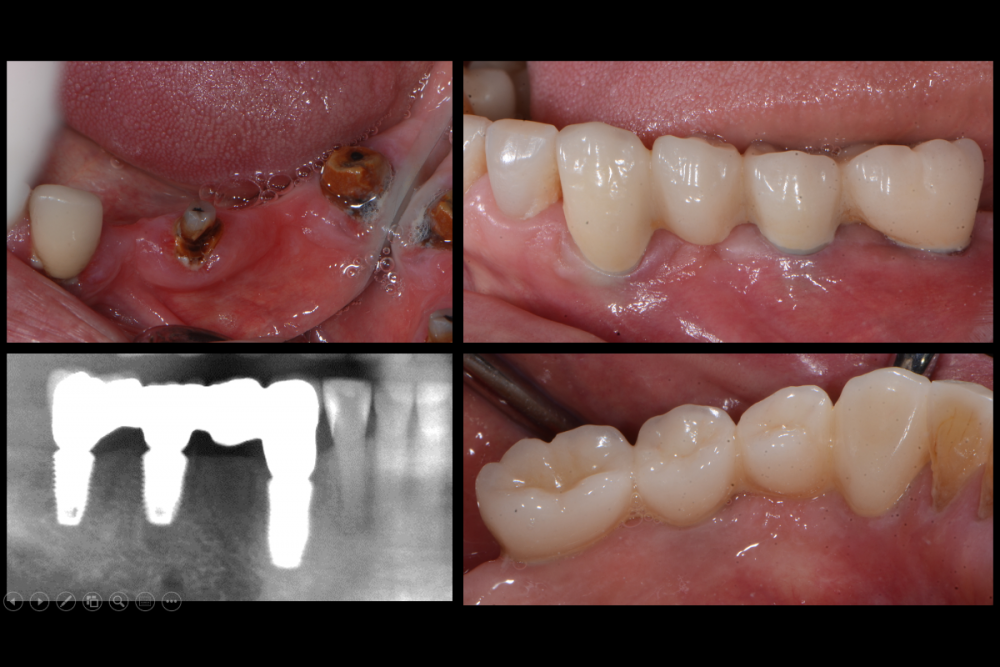

Карен Аванесов Опубликовано 3 августа, 2021 Поделиться Опубликовано 3 августа, 2021 (изменено) 1 визит хирургический протокол 2 визит оттиски 3 визит фиксация моста Какой бы нибыл приятный в общении пациент, частые встречи утомляют, думаю это обоюдно и со стороны пациентов (бесконечные хождения), так вот, если можно сократить количество визитов, почему бы это не сделать? Изменено 3 августа, 2021 пользователем Карен Аванесов 5 1 1 Ссылка на комментарий

Карен Аванесов Опубликовано 30 августа, 2021 Автор Поделиться Опубликовано 30 августа, 2021 14.08.2021 в 08:49, NickBulin сказал: Здравствуйте! Во время операций делаете ли r-снимки с пинами для контроля направления и заглубления? В данной работе хирургический протокол включал работу с мягкими тканями? Здравствуйте. Нет снимков не делал, после удаления и установкм имплантата в область клыка это был ориентир и пластику мягкотканную не использовал в данном ситуации. 14.08.2021 в 18:21, dentikl сказал: здравствуйте.На что клеили (если клеили)циркон?(если циркон). Здравствуйте. Да, Вы правы все циркон, циркон к циркону фиксирюю на жидклтекучий композит, после спиртовой ватки, пока ничего не "отлетало". Ссылка на комментарий

Карен Аванесов Опубликовано 28 сентября, 2021 Автор Поделиться Опубликовано 28 сентября, 2021 30.08.2021 в 23:03, dentikl сказал: Циркон к циркону под десной на жидкотекучий-просто Вы фартовый Механическая ретенция при идеально выполненом моделировании, как говорится хоть на сопли, ну и расположение уступа абатмента на уровне десны, не затрудняет устранение излишков цемента. Ссылка на комментарий